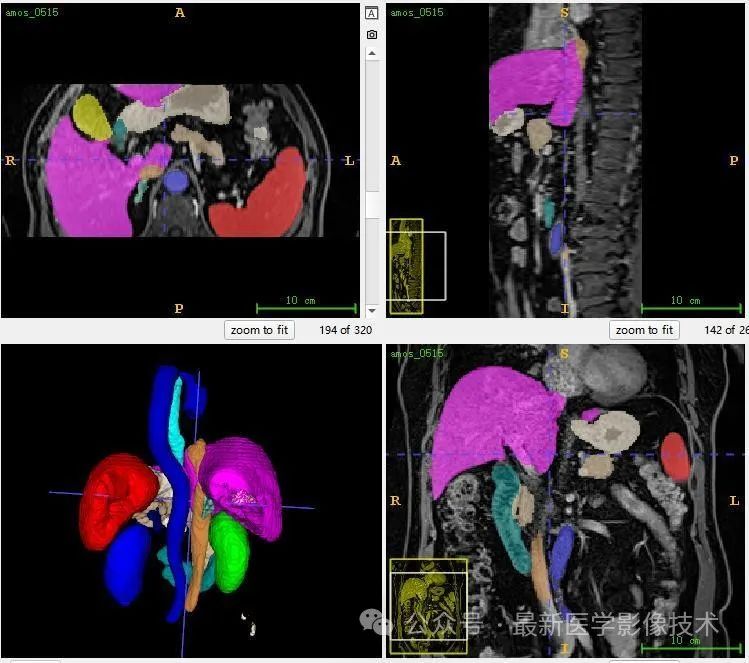

12、验证集分割结果

左图是金标准结果,右图是预测结果。

13、测试集分割结果